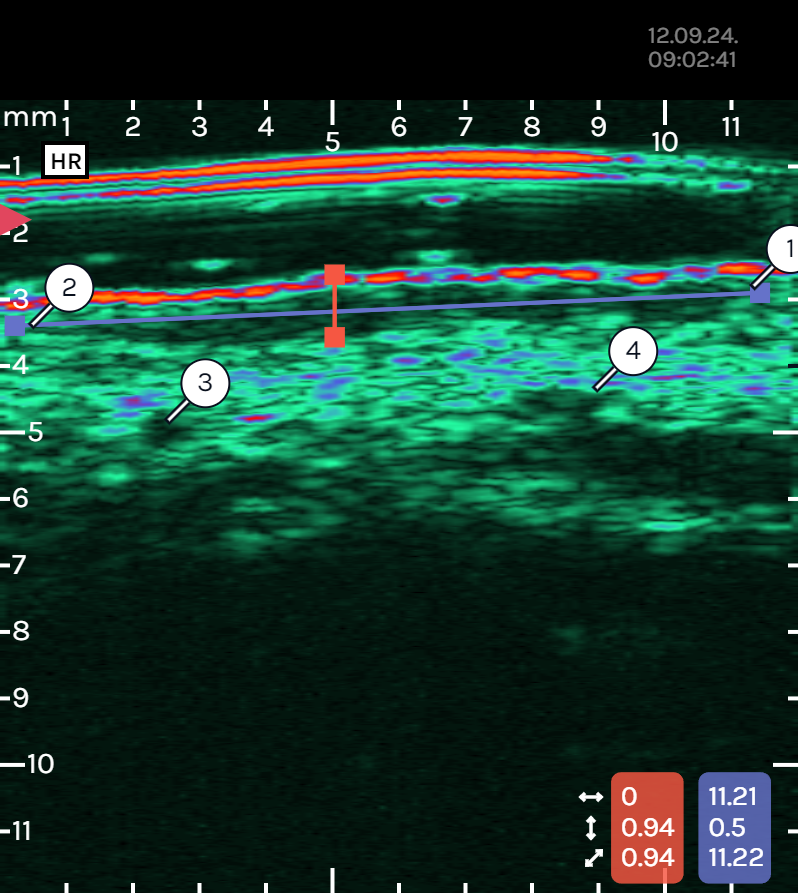

SkinScanner is a CE IIA MEDICAL DEVICE with EU MDR approval and an FDA pending application. The underlying technology is Dermoscopy-Assisted High-Frequency Ultrasound, which combines surface and depth imaging, making it simple and affordable. The technology is multimodal (providing more information), simultaneous (guided imaging), registered (for better interpretation), uses AI (for automated measurements), and is cloud-ready (for decentralized trials). The SkinScanner is portable, has the highest frequency, high resolution, and allows for single-hand operation.The High-Frequency Ultrasound is optimized for skin imaging in the 15-100MHz range. The specific Imaging Specifications for the ultrasound are:

- Frequency: 20-40 MHz

- Depth: up to 10 mm

- Field of view: $10 \text{mm} \text{(depth)} \times 12 \text{mm} \text{(loterol)}$

- Frame rate: $4+\text{fps}$

- Resolution: 100/300 $\mu\text{m}$The Optical field of view is $12 \text{mm} \times 12 \text{mm}$.

- Geometric: 2-point distance (thickness, diameter), AI-assisted segmentation (layer differentiation), and volume estimation.

- Doppler: Flow detection (along 1-D line currently), with 2-D Doppler under development.